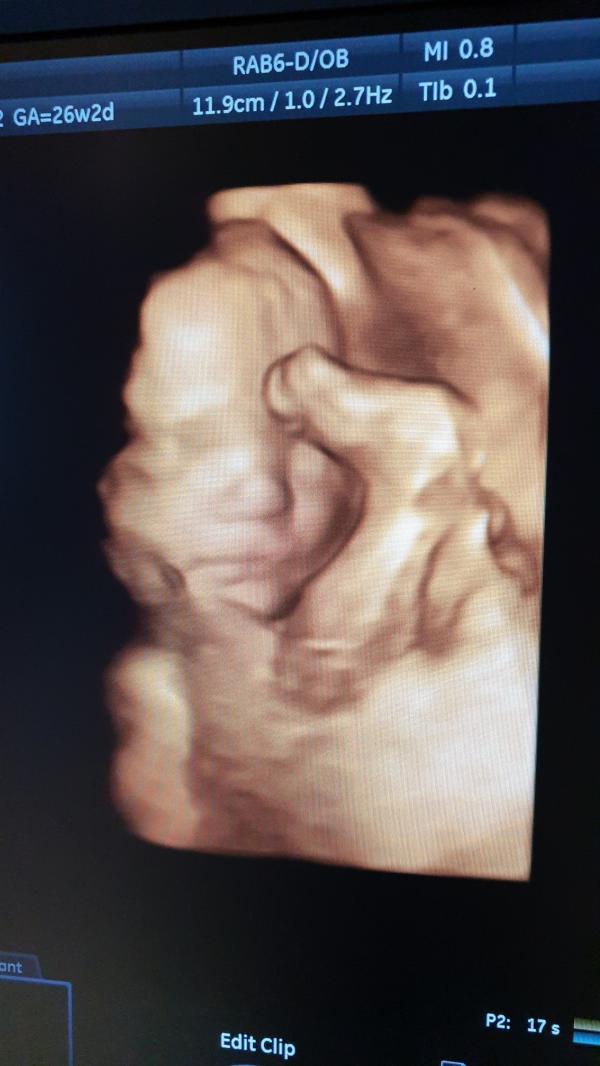

26 недель и 2 дня

Вес 911 гр

Чсс 141

Сказали длинноногий😄 (бедра и плечики на 27и5, ог 26и3, ож 25, бпр 27)

Перевернулся головой в низ🤗

Толщина плаценты 26, зрелость 0, нижний край на 70мм (поднялась 👍)

ИАЖ 14

ДШМ 3,1

Рубец 5,6 👌

Всё в порядке❤

Улыбался мне🥰 ножки задрал к голове, открывал рот... как потрясающе это всё наблюдать😍